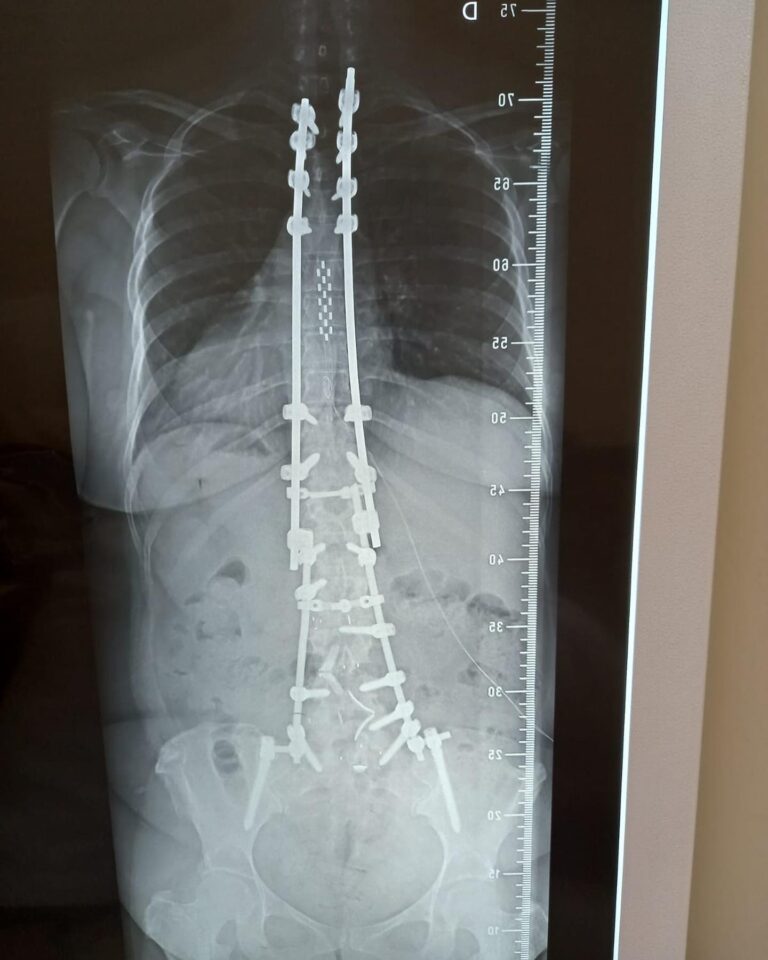

A cirurgia minimamente invasiva na coluna vertebral é um tipo de cirurgia que usa técnicas avançadas e instrumentação especializada para operar com mínima perturbação aos tecidos circundantes.

Pacientes com dores crônicas na coluna que não respondem a tratamentos conservadores, aqueles com discos herniados, estenose espinhal, fraturas vertebrais e algumas deformidades da coluna podem ser candidatos à cirurgia minimamente invasiva.

As taxas de sucesso variam dependendo da condição que está sendo tratada. No entanto, em geral, a cirurgia minimamente invasiva na coluna tem taxas de sucesso comparáveis, se não superiores, às dos procedimentos abertos tradicionais para muitas condições.